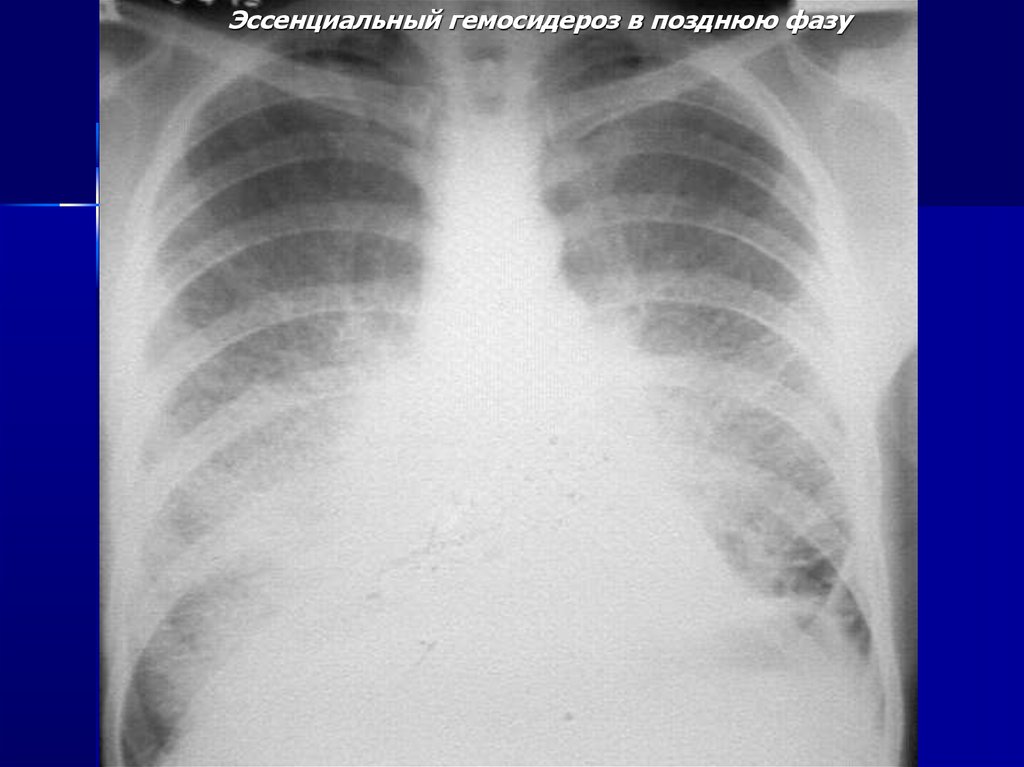

Эссенциальный гемосидероз в позднюю фазу